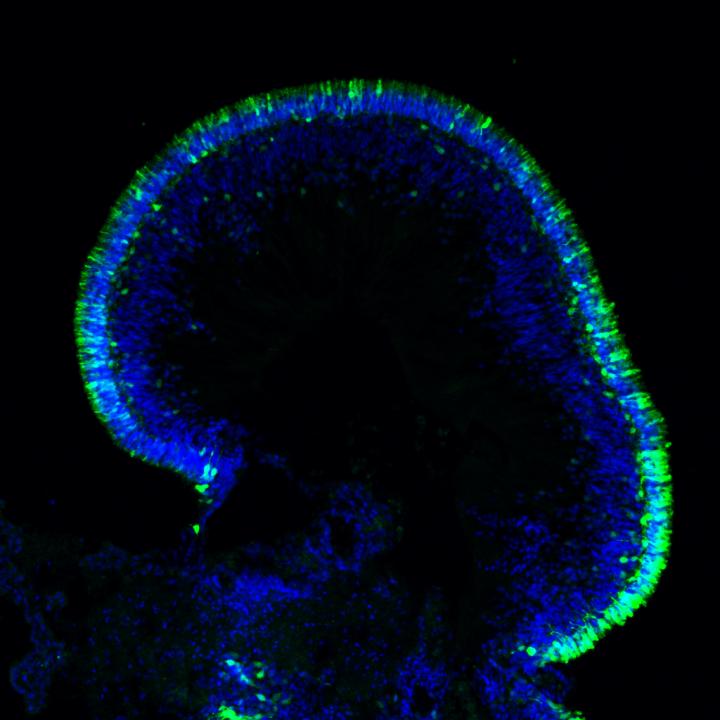

Retinal Organoid

image: Human retinal organoid. view more

Credit: Anand Swaroop, Ph.D., NEI

To explore how gene augmentation - adding copies of the normal gene - would affect autosomal-dominant LCA, Swaroop's team, developed retinal organoids from two volunteers with LCA and from their unaffected family members. Led by Kamil Kruczek, Ph.D., a postdoctoral fellow in Swaroop's lab, they built the complex retina-like tissues in several stages, starting with skin cells, inducing the production of mature photoreceptors and other retinal cells with the genetic profile of each volunteer. As expected, patient organoids made far less light-sensing opsin than the organoids made from unaffected family members.